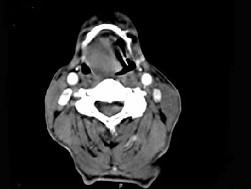

问题 男,74岁,咽喉部不适一年余,近两三个月咽喉疼痛,吞咽困难,CT如图所示,最可能诊断是 ( )

选项 A、声门下区癌 B、跨声门型癌 C、会厌癌 D、声带癌 E、喉癌

答案 C